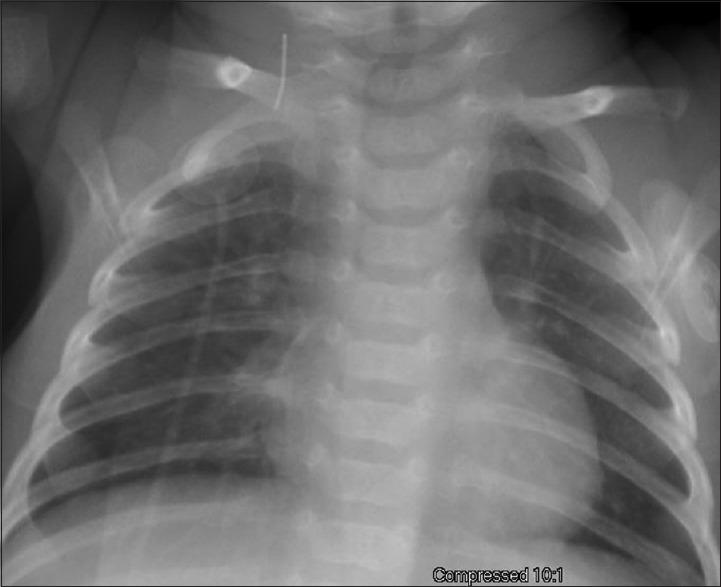

Retained intravascular foreign body is a well-known complication of central venous access placement in children as well as adults. Most of these foreign bodies are radio-opaque and hence are removed under fluoroscopy guidance. In our case, we describe the removal of an intracardiac radiolucent foreign body in an infant utilizing a combination technique - transesophageal echocardiogram and fluoroscopy.

血管内异物残留是儿童及成人中心静脉置管的一种常见并发症。这些异物大多是不透射线的,因此在荧光透视引导下取出。在我们的病例中,我们描述了采用经食管超声心动图和荧光透视联合技术为一名婴儿取出心内透射线异物的过程。